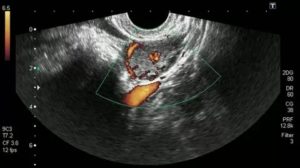

Как выглядит жёлтое тело на УЗИ

Желтое тело в левом яичнике

Жёлтое тело на УЗИ выглядит как маленький неоднородный пузырёк, располагающийся обычно с одной стороны яичника, немного выше его самого. Если на УЗИ не видно жёлтого тела, это может указывать на отсутствие овуляции либо очень маленький размер ЖТ. Во время процедуры можно обнаружить два жёлтых тела, такое возможно при:

3D визуализация желтого тела в яичнике

Выглядит на УЗИ желтое тело, как анэхогенное образование. Отсутствие эхогенности обусловлено его содержимым. Внутри находится жидкость, обрамленная ровным контуром без дополнительных камер. Находится желтое тело на поверхности яичника, где ранее располагался доминантный фолликул. Дополнительным показателем функции желтого тела становится толщина эндометрия.